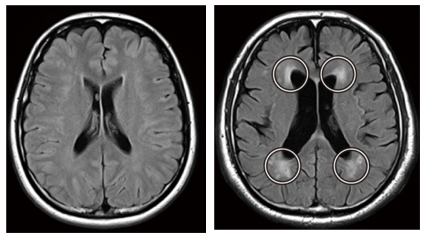

白質病変

右側の画像には白い斑点のように見える領域があります。

これは「白質病変」と呼ばれ、脳血管の虚血を表します。

(脳梗塞も虚血の一種です)

誰でも年齢とともに出現しますが、急速な増加は、将来の認知症や脳梗塞のリスク因子として知られています。